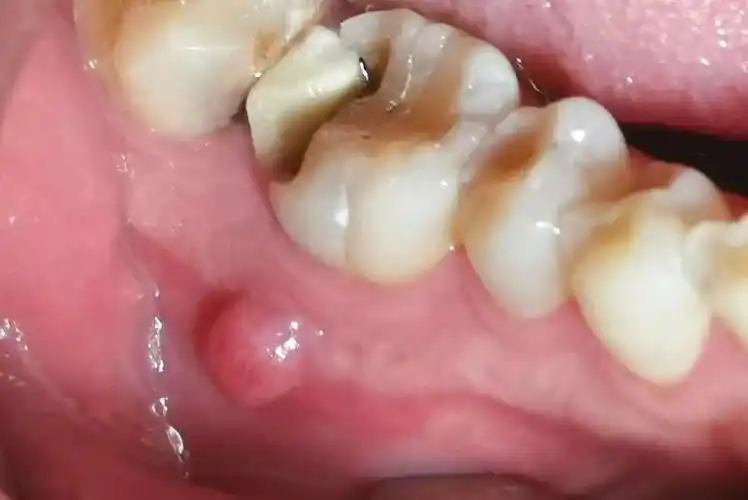

牙颌骨骨髓炎的症状图

如果有牙髓炎和根尖周炎,就需要接受根管治疗.何时需要根管治疗?